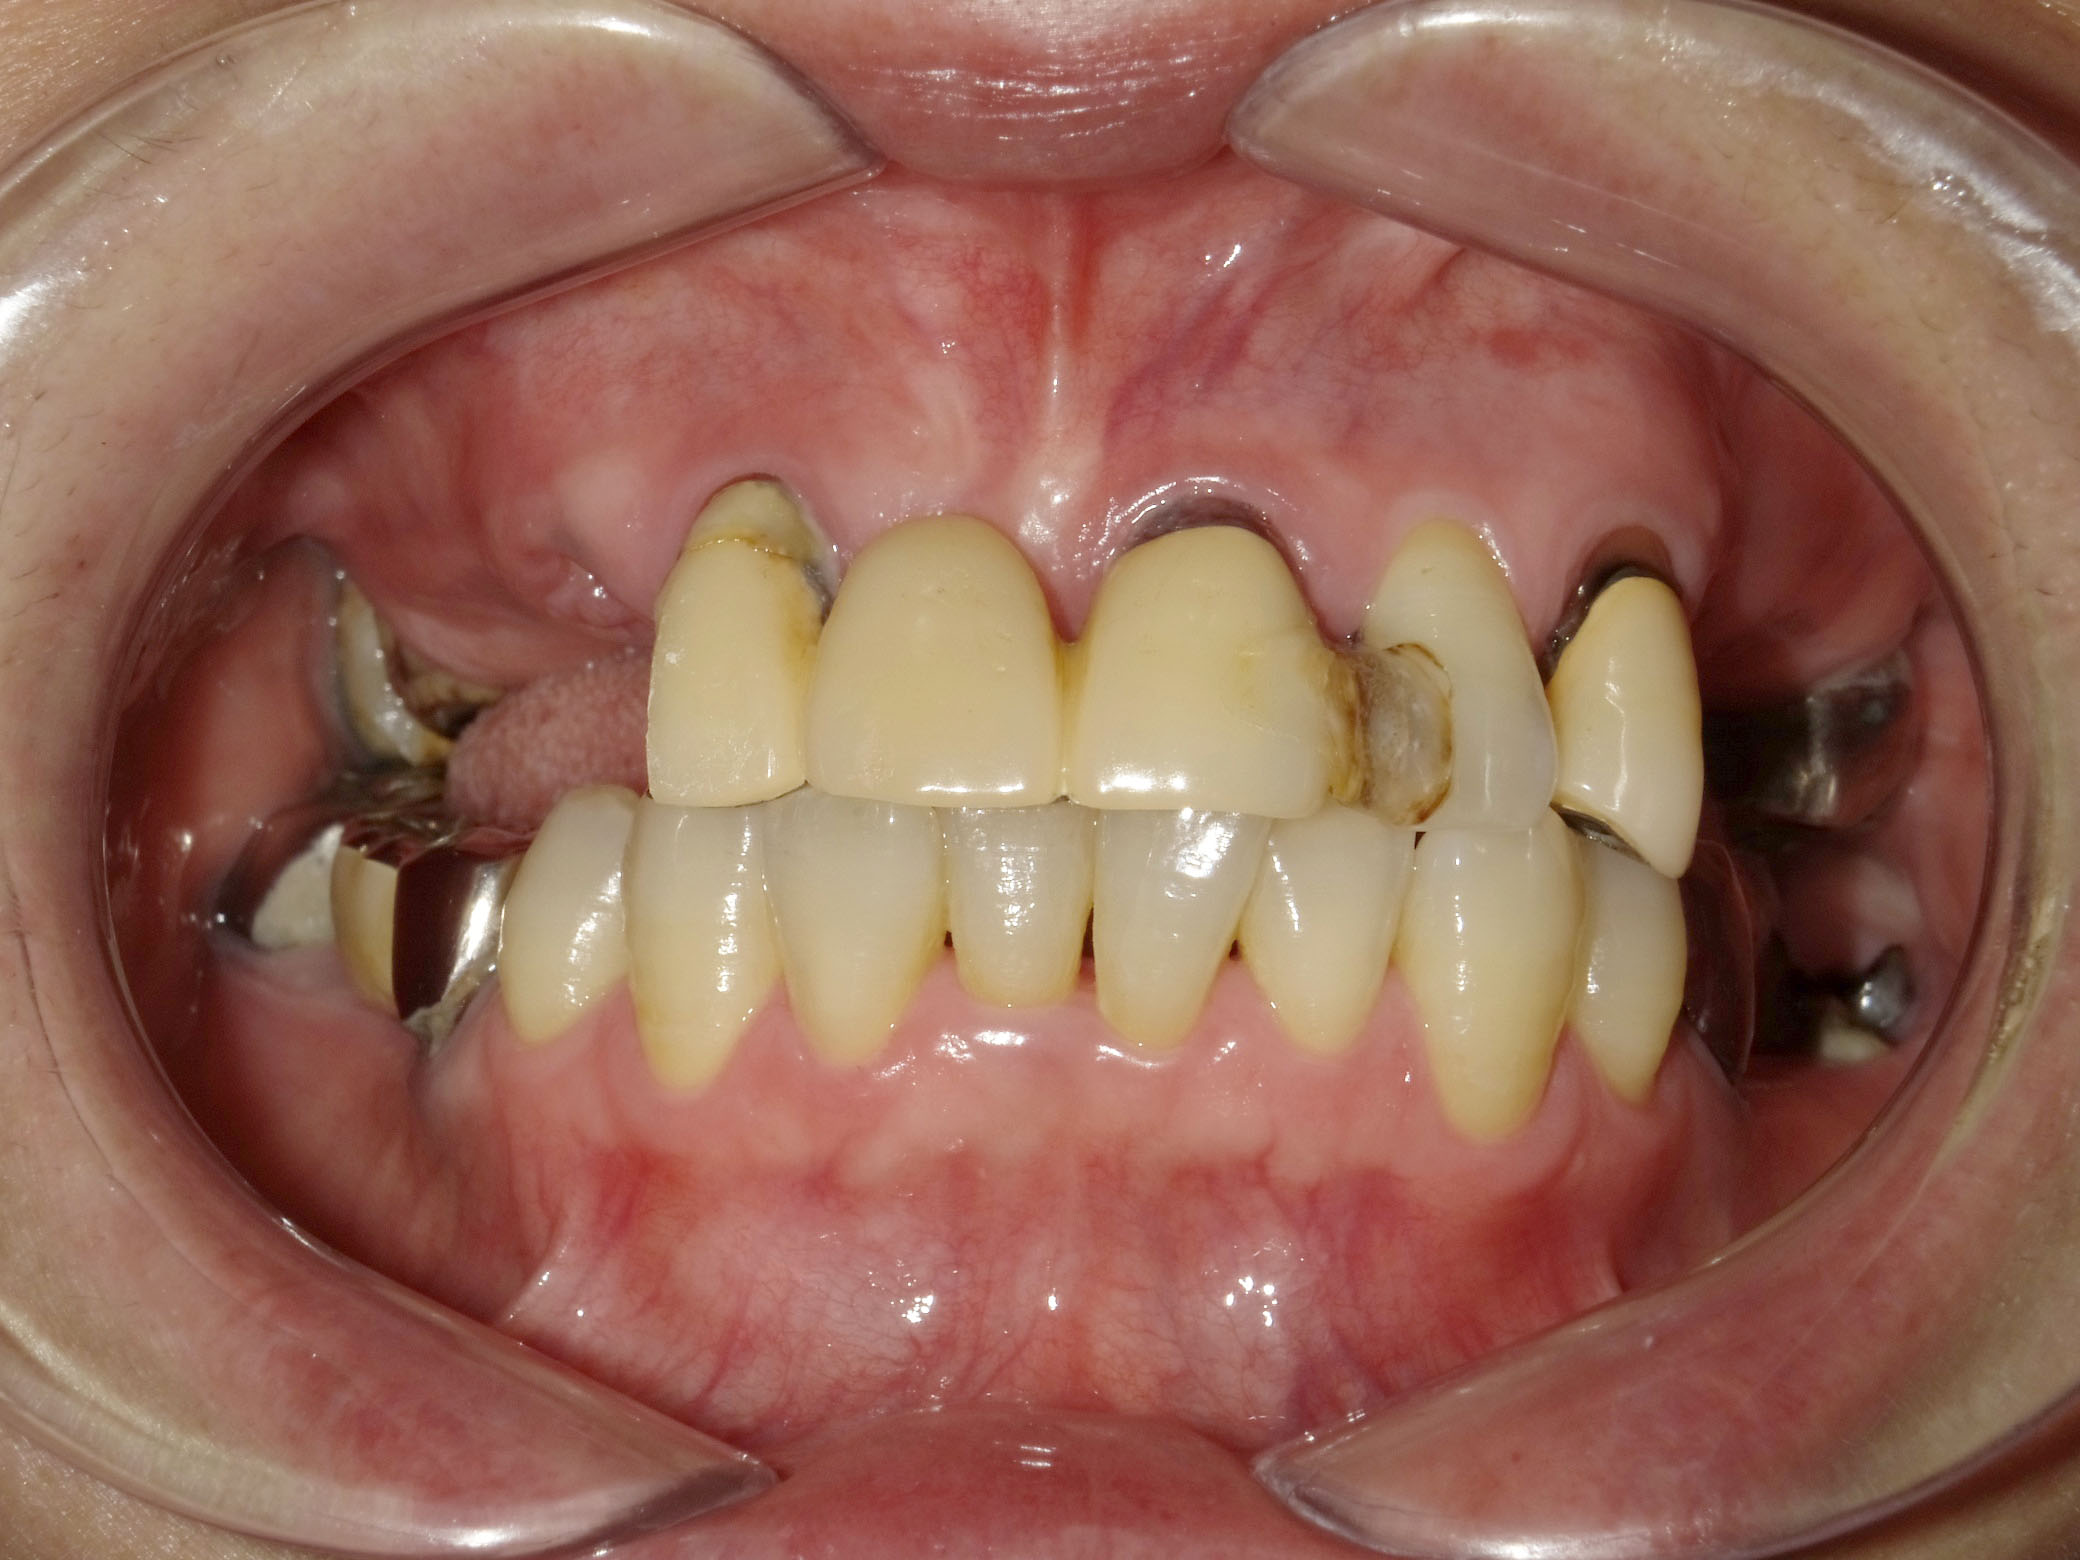

BEFORE

主訴

全体的に見た目を綺麗にしたい。奥歯でしっかり噛みたい。

診断名・主な症状

臼歯部欠損

年齢

70歳

治療内容

インプラント埋入(右上4・6,左上4・6,右下6,左下6)

ジルコニアBr(右上3―左上3)

ジルコニア(右下5,左下5)

治療期間/

通院回数

インプラント 1年5ヶ月/13回

ジルコニアBr、ジルコニアクラウン 3ヶ月/10回

費用

インプラント: 2,552,000円

その他治療: 640,000円

合計 3,192,000円

*いずれも税込